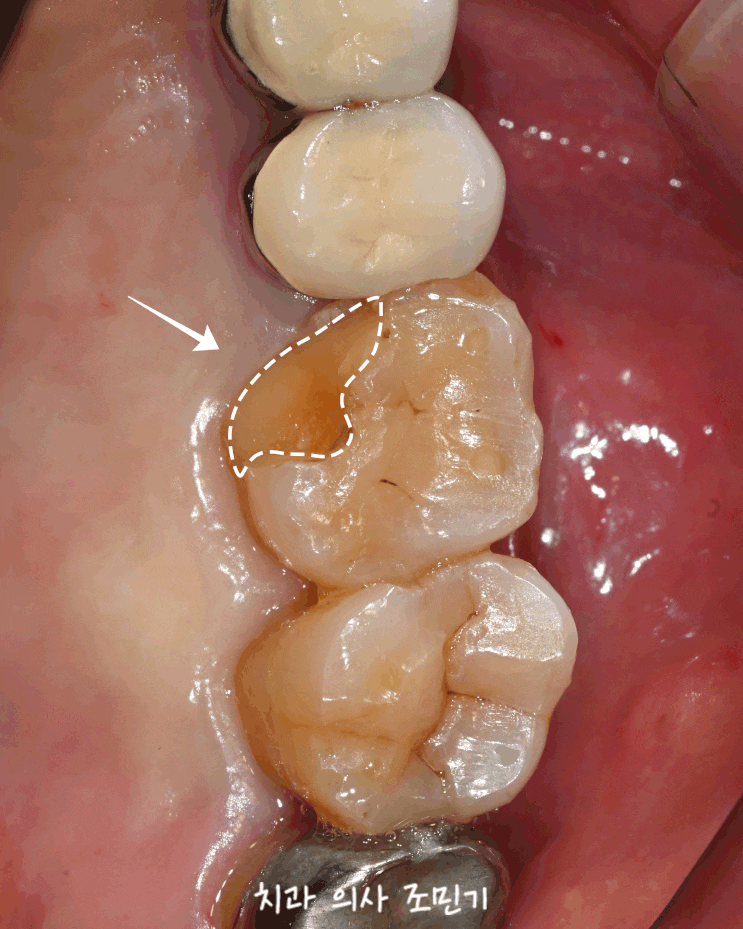

서대문구 치과 , 치아 가 시린 이유? 어금니 교합면 상아질 우식 진행 속도 , 레진 충전 충치 치료 케이스

반갑습니다. 서대문구 치과 의사 조민기입니다. 이에 거뭇거뭇한 점이 있어요! 만약 어금니 에 이런 점이 ...